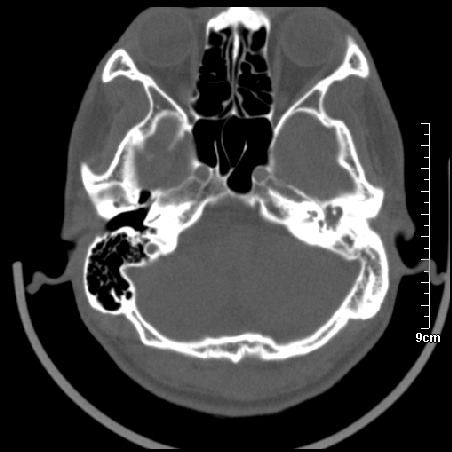

病例1

m/46y 头晕.耳鸣半月余 有乳突炎病史

病例2

m/27

胆脂瘤是是以鳞状上皮内衬充满角质化碎片的囊,随着角化屑片的不断堆积,肿块逐渐增大,胆脂瘤可为先天性(2%)或后天性(98%)。胆脂瘤有感染史。中耳内的鳞状上皮通常有外耳道的上皮通过一鼓膜的缺损移行至中耳,其他的原因包括鳞状上皮化生。由于欧氏管的功能不全所引起的中耳负压可产生上鼓室鼓膜松弛部的牵引性开袋。继而发展成胆脂瘤。成年人胆脂瘤时乳突常发育差,而儿童常有广泛性乳突气化,这种气化可导致胆脂瘤的更广泛的乳突扩散。后天性胆脂瘤患者大多数存在骨质破坏。

松弛部胆脂瘤有中央性穿孔或后上部牵引口袋所致。紧张部胆脂瘤经常侵蚀听小骨并引起传导性耳聋。

中耳胆脂瘤有两个重要并发症:一是面神经管的水平段受暴露,二是外侧半规管受侵蚀产生瘘管。面神经在ct上难以显示或不可能显示,除非其周围有空气包绕或有良好轮廓的骨性覆盖。胆脂瘤还可合并感染,产生于急性中耳炎.乳突炎所描述的那些合并症。

左侧板障型乳突。

左侧慢性中耳炎伴胆脂瘤形成。

左中耳乳突炎合并胆脂瘤形成